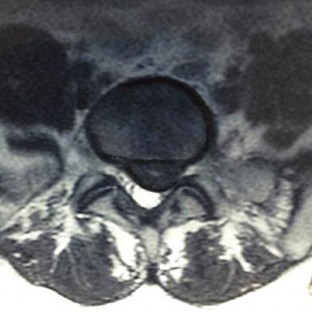

A 60-year-old male with poorly controlled diabetes mellitus presents with severe back pain, fever, and progressive bilateral lower extremity weakness over the past 24 hours. An urgent MRI confirms an anterior epidural abscess at L2-L3.

Blood cultures are drawn. What is the next best step in management?